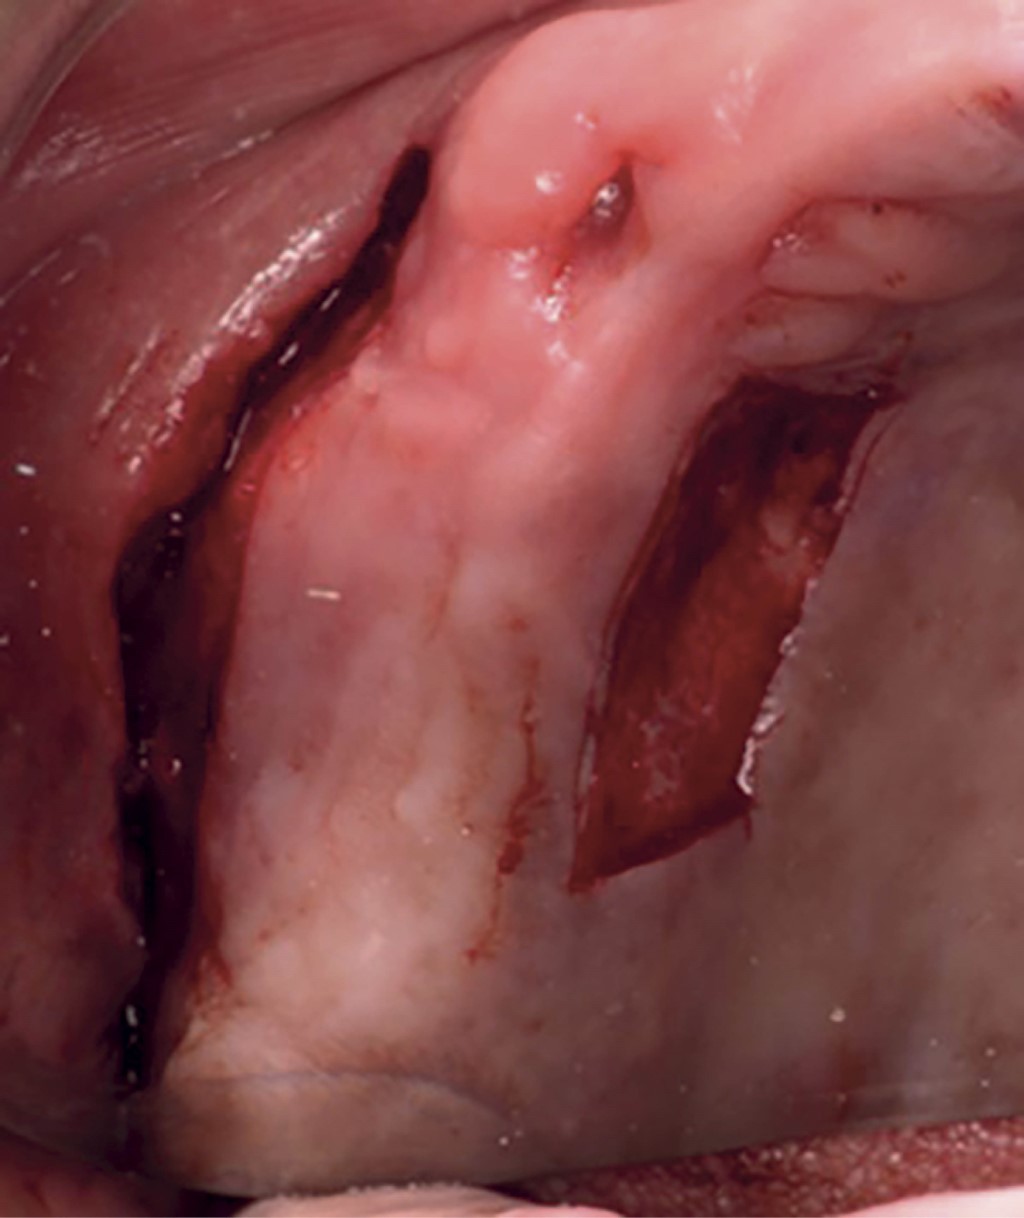

El procedimiento quirúrgico se llevó a cabo bajo anestesia local, mediante las técnicas de alveolares posteriores superiores, alveolares medios, técnica infraorbitaria en la zona receptora de la vestibuloplastia. Para la toma del IGL se anestesió mediante la técnica palatina mayor y nasopalatina. Se inició con una incisión a nivel de la línea mucogingival con descarga distal y mesial y posteriormente se continuó con la elevación de un colgajo parcial y la disección de las fibras musculares (Figura 2). Una vez preparado el lecho receptor, se procedió a la toma del IGL de la mucosa palatina y se realizó la disección del injerto para obtener un grosor de 1 mm aproximadamente (Figuras 3 y 4). Luego, se colocó el IGL en la zona receptora y se fijó mediante puntos simples con Vicryl 5.0 en los extremos del injerto al periostio, seguido de puntos en X fijados en el periostio en la zona apical y en la encía queratinizada hacia el reborde. Finalmente, se colocaron puntos simples para llevar el borde bucal de la herida hacia la porción más apical (Figura 5).

Figura 3

Figura 4